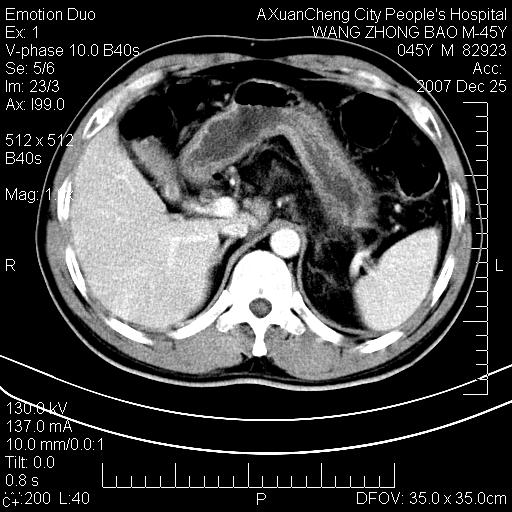

以下是引用卜一在2007-12-25 14:07:00的发言:[br]胰头钩部略增大,与十二指肠壶腹部关系密切,其内明显见软组织密度肿块,明显强化,但肠壁较光滑 柔软。考虑:炎性增生!建议消炎后复查!待除外壶腹部腺癌!

以下是引用zjzjr在2007-12-25 13:35:00的发言:[br]考虑正常的十二指肠乳头部,建议胃镜检查.

以下是引用qiuleiyu在2007-12-25 18:14:00的发言:[br]胰腺增大,周边渗出改变,肾前筋膜明显增厚,示少量积液.胆囊壁毛糙,周边少许渗出,胆总管壁厚,异常强化,然扩张不明显.结合病程急短;考虑;胆管炎,胆囊炎,胆源性胰腺炎可能大,请结合实验室检查及随访.

以下是引用lisihao在2007-12-25 14:23:00的发言:[br]急性水肿型胰腺炎[br]依据:1、胰腺弥漫性肿大,边缘稍毛糙;[br] 2、双侧肾周筋膜增厚,尤以左侧为甚(重要征象)[br] 3、双侧后胸膜增厚(刺激性炎症);[br] 4、结合病史,查血尿淀粉酶应该可以确诊。